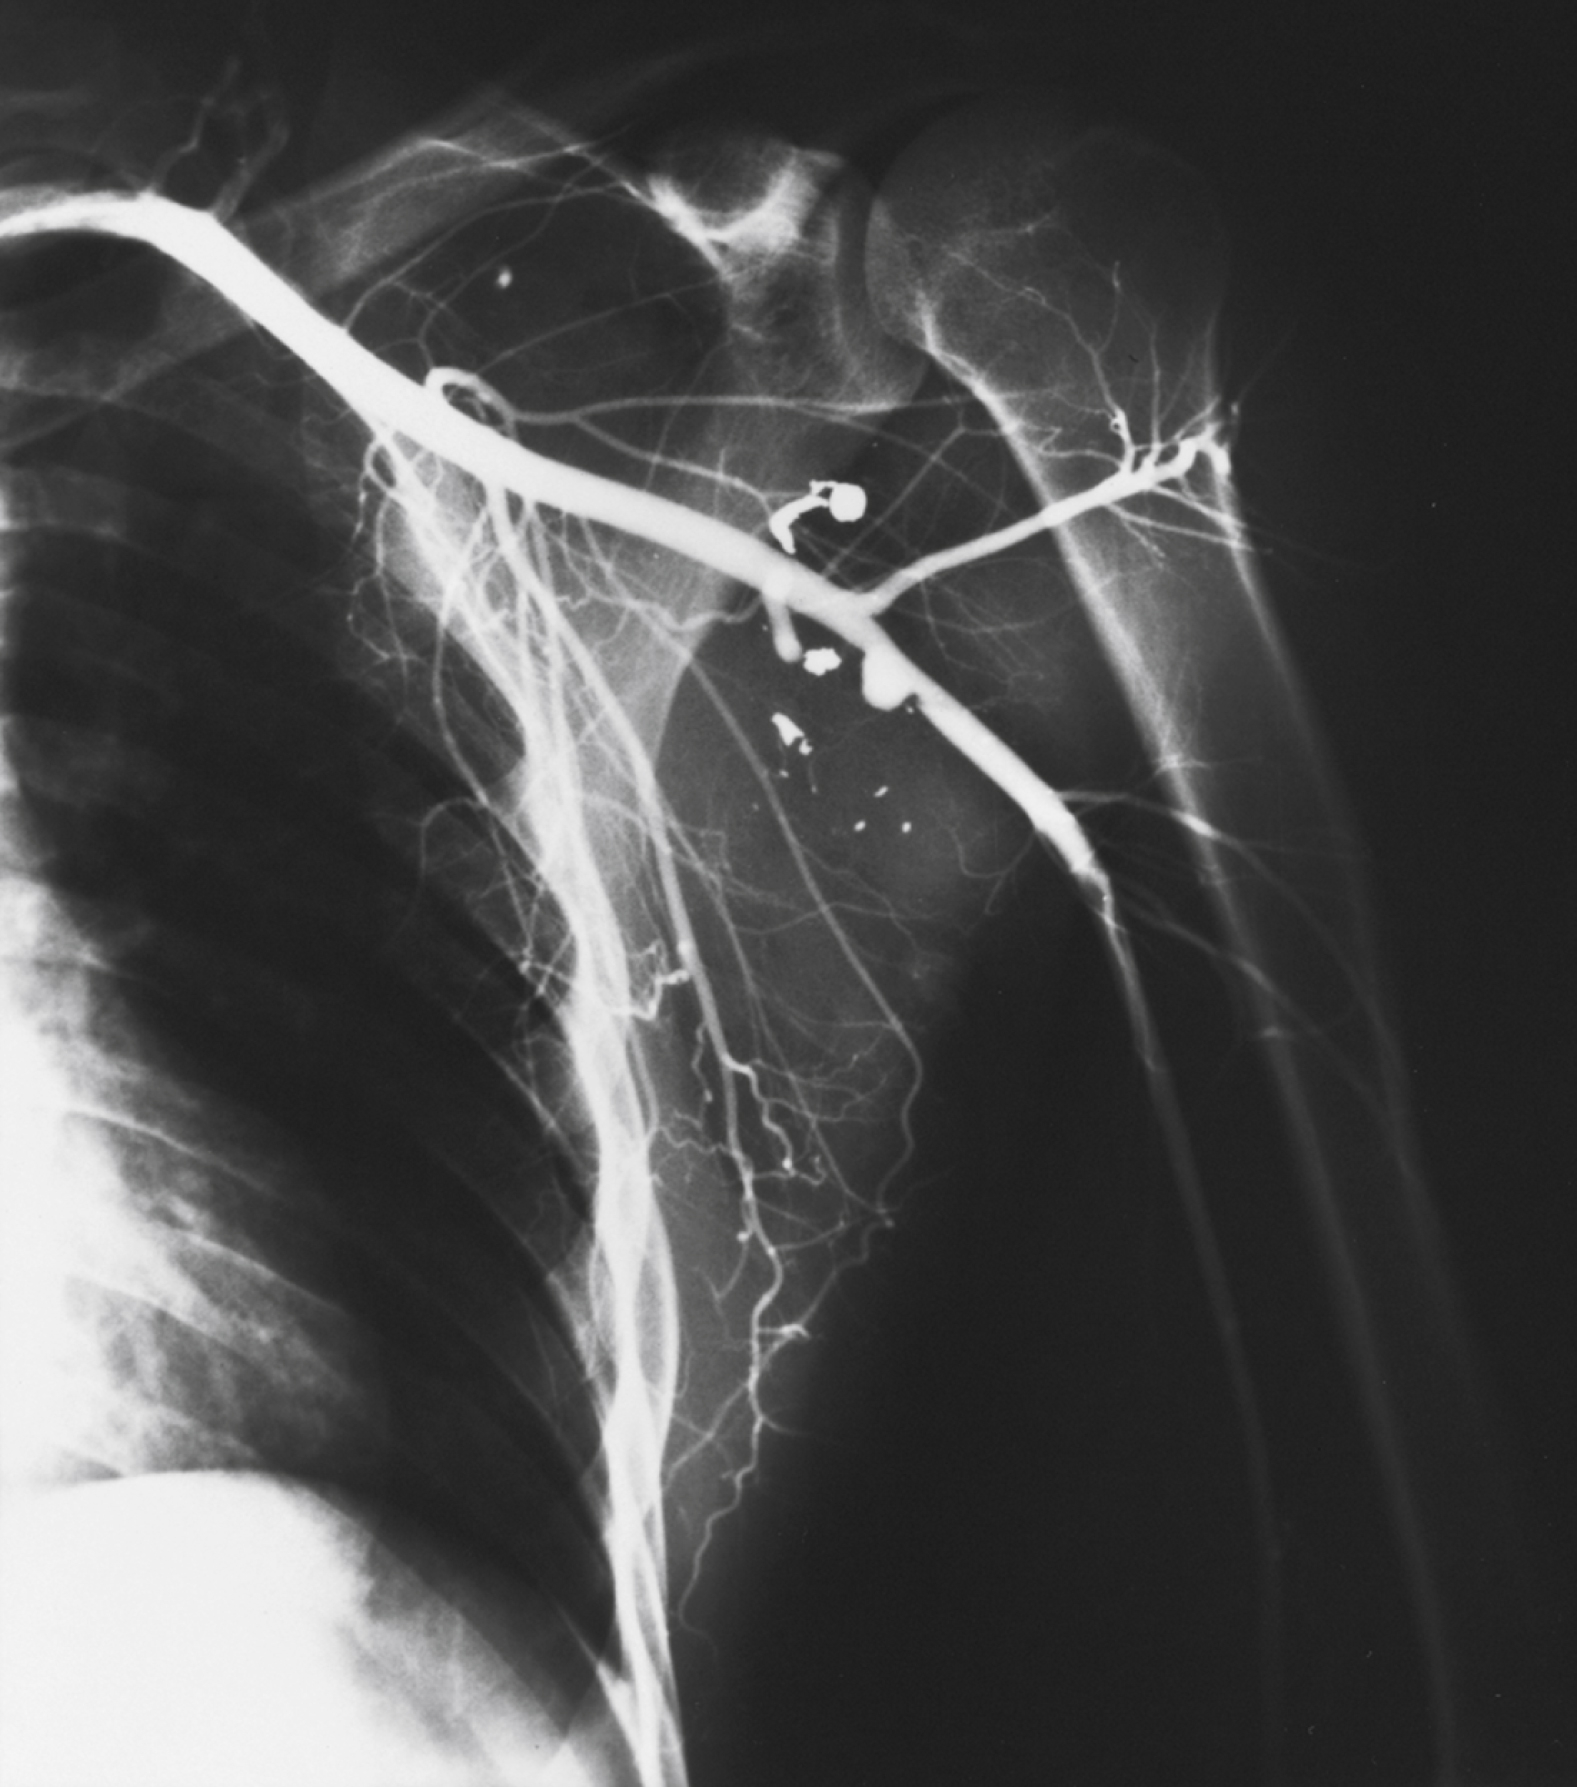

A true aneurysm contains all three layers of the vessel wall (intima, media, and adventitia) and is rarely caused by trauma. A pseudoaneurysm is formed following a tear in a vessel wherein the hemorrhage is contained by surrounding fascia and the resulting hematoma is gradually encased by a capsule of fibrous tissue, analogous in consistency to the adventitia of a normal vessel ( Fig. 40.5 ). Because it is relatively thin walled, rupture of a pseudoaneurysm is a distinct possibility. In addition, because its diameter inevitably expands under arterial pressure over days to months, compression of adjacent tissue may result in neuropathy, venous obstruction with resultant peripheral edema and venous thrombosis, and even erosion into adjacent bone. The cavity of a pseudoaneurysm is in direct communication with the lumen of the vessel, so embolization of mural clots may produce distal arterial occlusion. Pseudoaneurysms may be diagnosed months to years after an injury when a patient manifests symptoms of compression neuropathy or peripheral arterial embolism or for investigation of a soft tissue “tumor” that represents the growing aneurysm.

Multiple small pseudoaneurysms of the axillary artery after penetrating injury.

Courtesy D. Demetreades, MD.